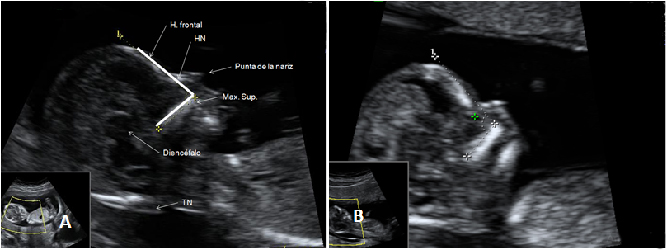

La ecografía en tres dimensiones muestra un feto de 13 semanas de gestación con el cordón umbilical alrededor del cuello. En la imagen rotatoria se puede observar la situación del cordón, que sube por el tórax y que seguramente puede causar complicaciones en el embarazo.